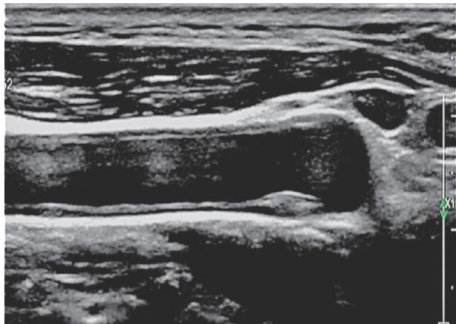

摘要目的应用膈肌超声评估体外膈肌起搏联合腹式呼吸训练治疗慢性阻塞性肺疾病(COPD)的疗效,探讨其临床价值。方法选取我院收治的COPD患者98例,采用随机数字表法将其分为对照组(采用常规基础治疗联合腹式呼吸训练)和研究组(采用体外膈肌起搏治疗联合腹式呼吸训练),每组各49例,治疗4周后应用超声获取平静呼吸时膈肌移动度( DMQB )、深吸气时膈肌移动度 ΔDMDB )、功能残气时相膈肌厚度( ΔTDFRC )、肺总量时相膈肌厚度( ΔTDTLC, 及厚度分数(TF);肺功能检查获取第1秒用力呼吸容积( FEV1 )、用力肺活量(FVC)、FEV/FVC、每分钟最大通气量(MVV)及最大呼气流速(PEF),呼吸肌力测试仪获取最大口腔吸气压( CPMIP. )、最大口腔呼气压( ΔCPMEP )及口腔阻断压 (P0.1) ,比较两组治疗总有效率及治疗前后上述指标的差异。结果两组治疗后 FEV1,FVC,FEV1/FVC,MVV,PEFCPMP?CPMEP 均高于治疗前, P0.1 低于治疗前,研究组治疗后 FEV1 FEV/FVC、MVV、PEF、 CPMIP,CPMEP 均高于对照组, P0.1 低于对照组,差异均有统计学意义(均 P<0.05 )。两组治疗后 DMQB,DMDB,TDFRC,TDTLC, F均大于治疗前,且研究组大于对照组,差异均有统计学意义(均 P<0.05 )。研究组与对照组总有效率分别为 89.80%.73.47% ,差异有统计学意义 (χ2=4.356,P=0.037) 。研究组治疗后有效者 DM0B?DMDB?TDFRC?TDTLC. TF均大于治疗前及无效者,差异均有统计学意义(均 P<0.05 )。结论膈肌超声在体外膈肌起搏联合腹式呼吸训练治疗COPD疗效评估中具有一定的临床价值。